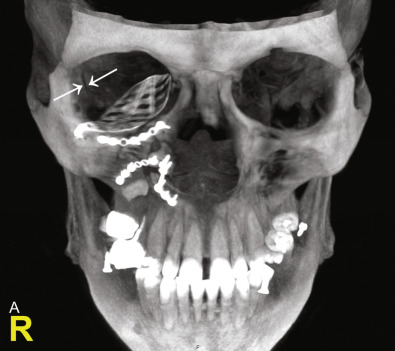

Basically, the indications are more or less the same as compared to conventional postoperative CBCT or CT. The major advantage of intraoperative imaging can be seen in procedures in which intraoperative verification of the surgical result is crucial and would lead to secondary corrections. According to recent literature, the major indication for intraoperative CBCT is craniomaxillofacial trauma, particularly fractures of the zygomaticomaxillary complex (ZMC), including posttraumatic orbital deformities. However, multiple different indications have been described in the literature. Intraoperative CBCT has also been used in orthognathic surgery, in maxillary and mandibular reconstructions with bone grafts. In gunshot injuries it was shown to be useful in the detection and removal of metallic foreign bodies. Intraoperative imaging using a 3D C-arm was used during mandibular fracture repair, particularly of the condylar process and the condylar head. In those cases the postreduction result of the fragments or the position of the condylar head in the glenoid fossa are crucial. Three-dimensional intraoperative imaging using a C-arm device was also described as a practical device in evaluation and verification following bone grafting procedures, including sinus floor augmentation. Furthermore, CBCT data generated by intraoperative mobile systems were shown to be sufficient for the planning of dental implant position. As mentioned above, intraoperative imaging can also be used in combination with intraoperative real-time navigation. Finally, preoperative CT or MRI in infants often requires general anesthesia. In children with preoperatively proven indications for surgical treatment, preoperative imaging under general anesthesia was substituted by intraoperative CBCT scans.

There are various markers that can be used for registration, including anatomical landmarks, dental-based navigation splints with radiopaque markers (screws), or previously inserted navigation screws. Anatomical landmarks for registration can be defined using the initial CT or CBCT scan. However, an additional CT or CBCT scan is required in case navigation splints or navigation screws are used ( Fig. 1.3.3B ). Meanwhile, frameless registration can be realized in the craniomaxillofacial region using a laser surface scanning system in order to avoid radiation exposure. Computer-assisted preoperative planning is required to virtually reduce fractures or reconstruct defects by mirroring. Intraoperatively, the patient’s position and anatomy need to be registered to the preoperative CT or CBCT data set using a “skull reference base” that needs to be fixed to the patient’s skull. Thereby, the patient’s position during the procedure can be tracked. Intraoperatively, the quality of fracture reduction as well as the planned position and shape of an implant can be checked in real-time sensing. It could be shown that intraoperative infrared-based navigation significantly improves the precision of orbital reconstruction using different titanium implants. The use of navigation also had a significant effect on the precision of the orbital volume reconstruction.